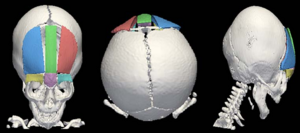

Accuracy of Open-Source Software Segmentation and Paper-based Printed Three-Dimensional Models

Publication: J Craniomaxillofac Surg. 2016 Feb;44(2):202-9. PMID: 26748414 Authors: Szymor P, Kozakiewicz M, Olszewski R. Institution: Department of Maxillofacial Surgery, Medical University of Lodz, Lodz, Poland. Background/Purpose: In this study, we aimed to verify the accuracy of models created with the help of open-source 3D Slicer 3.6.3 software (Surgical Planning Lab, Harvard Medical School, Harvard University, Boston, MA, USA) and the Mcor Matrix 300 paper-based 3D printer. Our study focused on the accuracy of recreating the walls of the right orbit of a cadaveric skull. Cone beam computed tomography (CBCT) of the skull was performed (0.25-mm pixel size, 0.5-mm slice thickness). Acquired DICOM data were imported into 3D Slicer 3.6.3 software, where segmentation was performed. A virtual model was created and saved as an .STL file and imported into Netfabb Studio professional 4.9.5 software. Three different virtual models were created by cutting the original file along three different planes (coronal, sagittal, and axial). All models were printed with a Selective Deposition Lamination Technology Matrix 300 3D printer using 80 gsm A4 paper. The models were printed so that their cutting plane was parallel to the paper sheets creating the model. Each model (coronal, sagittal, and axial) consisted of three separate parts (∼200 sheets of paper each) that were glued together to form a final model. The skull and created models were scanned with a three-dimensional (3D) optical scanner (Breuckmann smart SCAN) and were saved as .STL files. Comparisons of the orbital walls of the skull, the virtual model, and each of the three paper models were carried out with GOM Inspect 7.5SR1 software. Deviations measured between the models analysed were presented in the form of a colour-labelled map and covered with an evenly distributed network of points automatically generated by the software. An average of 804.43 ± 19.39 points for each measurement was created. Differences measured in each point were exported as a .csv file. The results were statistically analysed using Statistica 10, with statistical significance set at p < 0.05. The average number of points created on models for each measurement was 804.43 ± 19.39; however, deviation in some of the generated points could not be calculated, and those points were excluded from further calculations. From 94% to 99% of the measured absolute deviations were <1 mm. The mean absolute deviation between the skull and virtual model was 0.15 ± 0.11 mm, between the virtual and printed models was 0.15 ± 0.12 mm, and between the skull and printed models was 0.24 ± 0.21 mm. Using the optical scanner and specialized inspection software for measurements of accuracy of the created parts is recommended, as it allows one not only to measure 2-dimensional distances between anatomical points but also to perform more clinically suitable comparisons of whole surfaces. However, it requires specialized software and a very accurate scanner in order to be useful. Threshold-based, manually corrected segmentation of orbital walls performed with 3D Slicer software is accurate enough to be used for creating a virtual model of the orbit. The accuracy of the paper-based Mcor Matrix 300 3D printer is comparable to those of other commonly used 3-dimensional printers and allows one to create precise anatomical models for clinical use. The method of dividing the model into smaller parts and sticking them together seems to be quite accurate, although we recommend it only for creating small, solid models with as few parts as possible to minimize shift associated with gluing. |